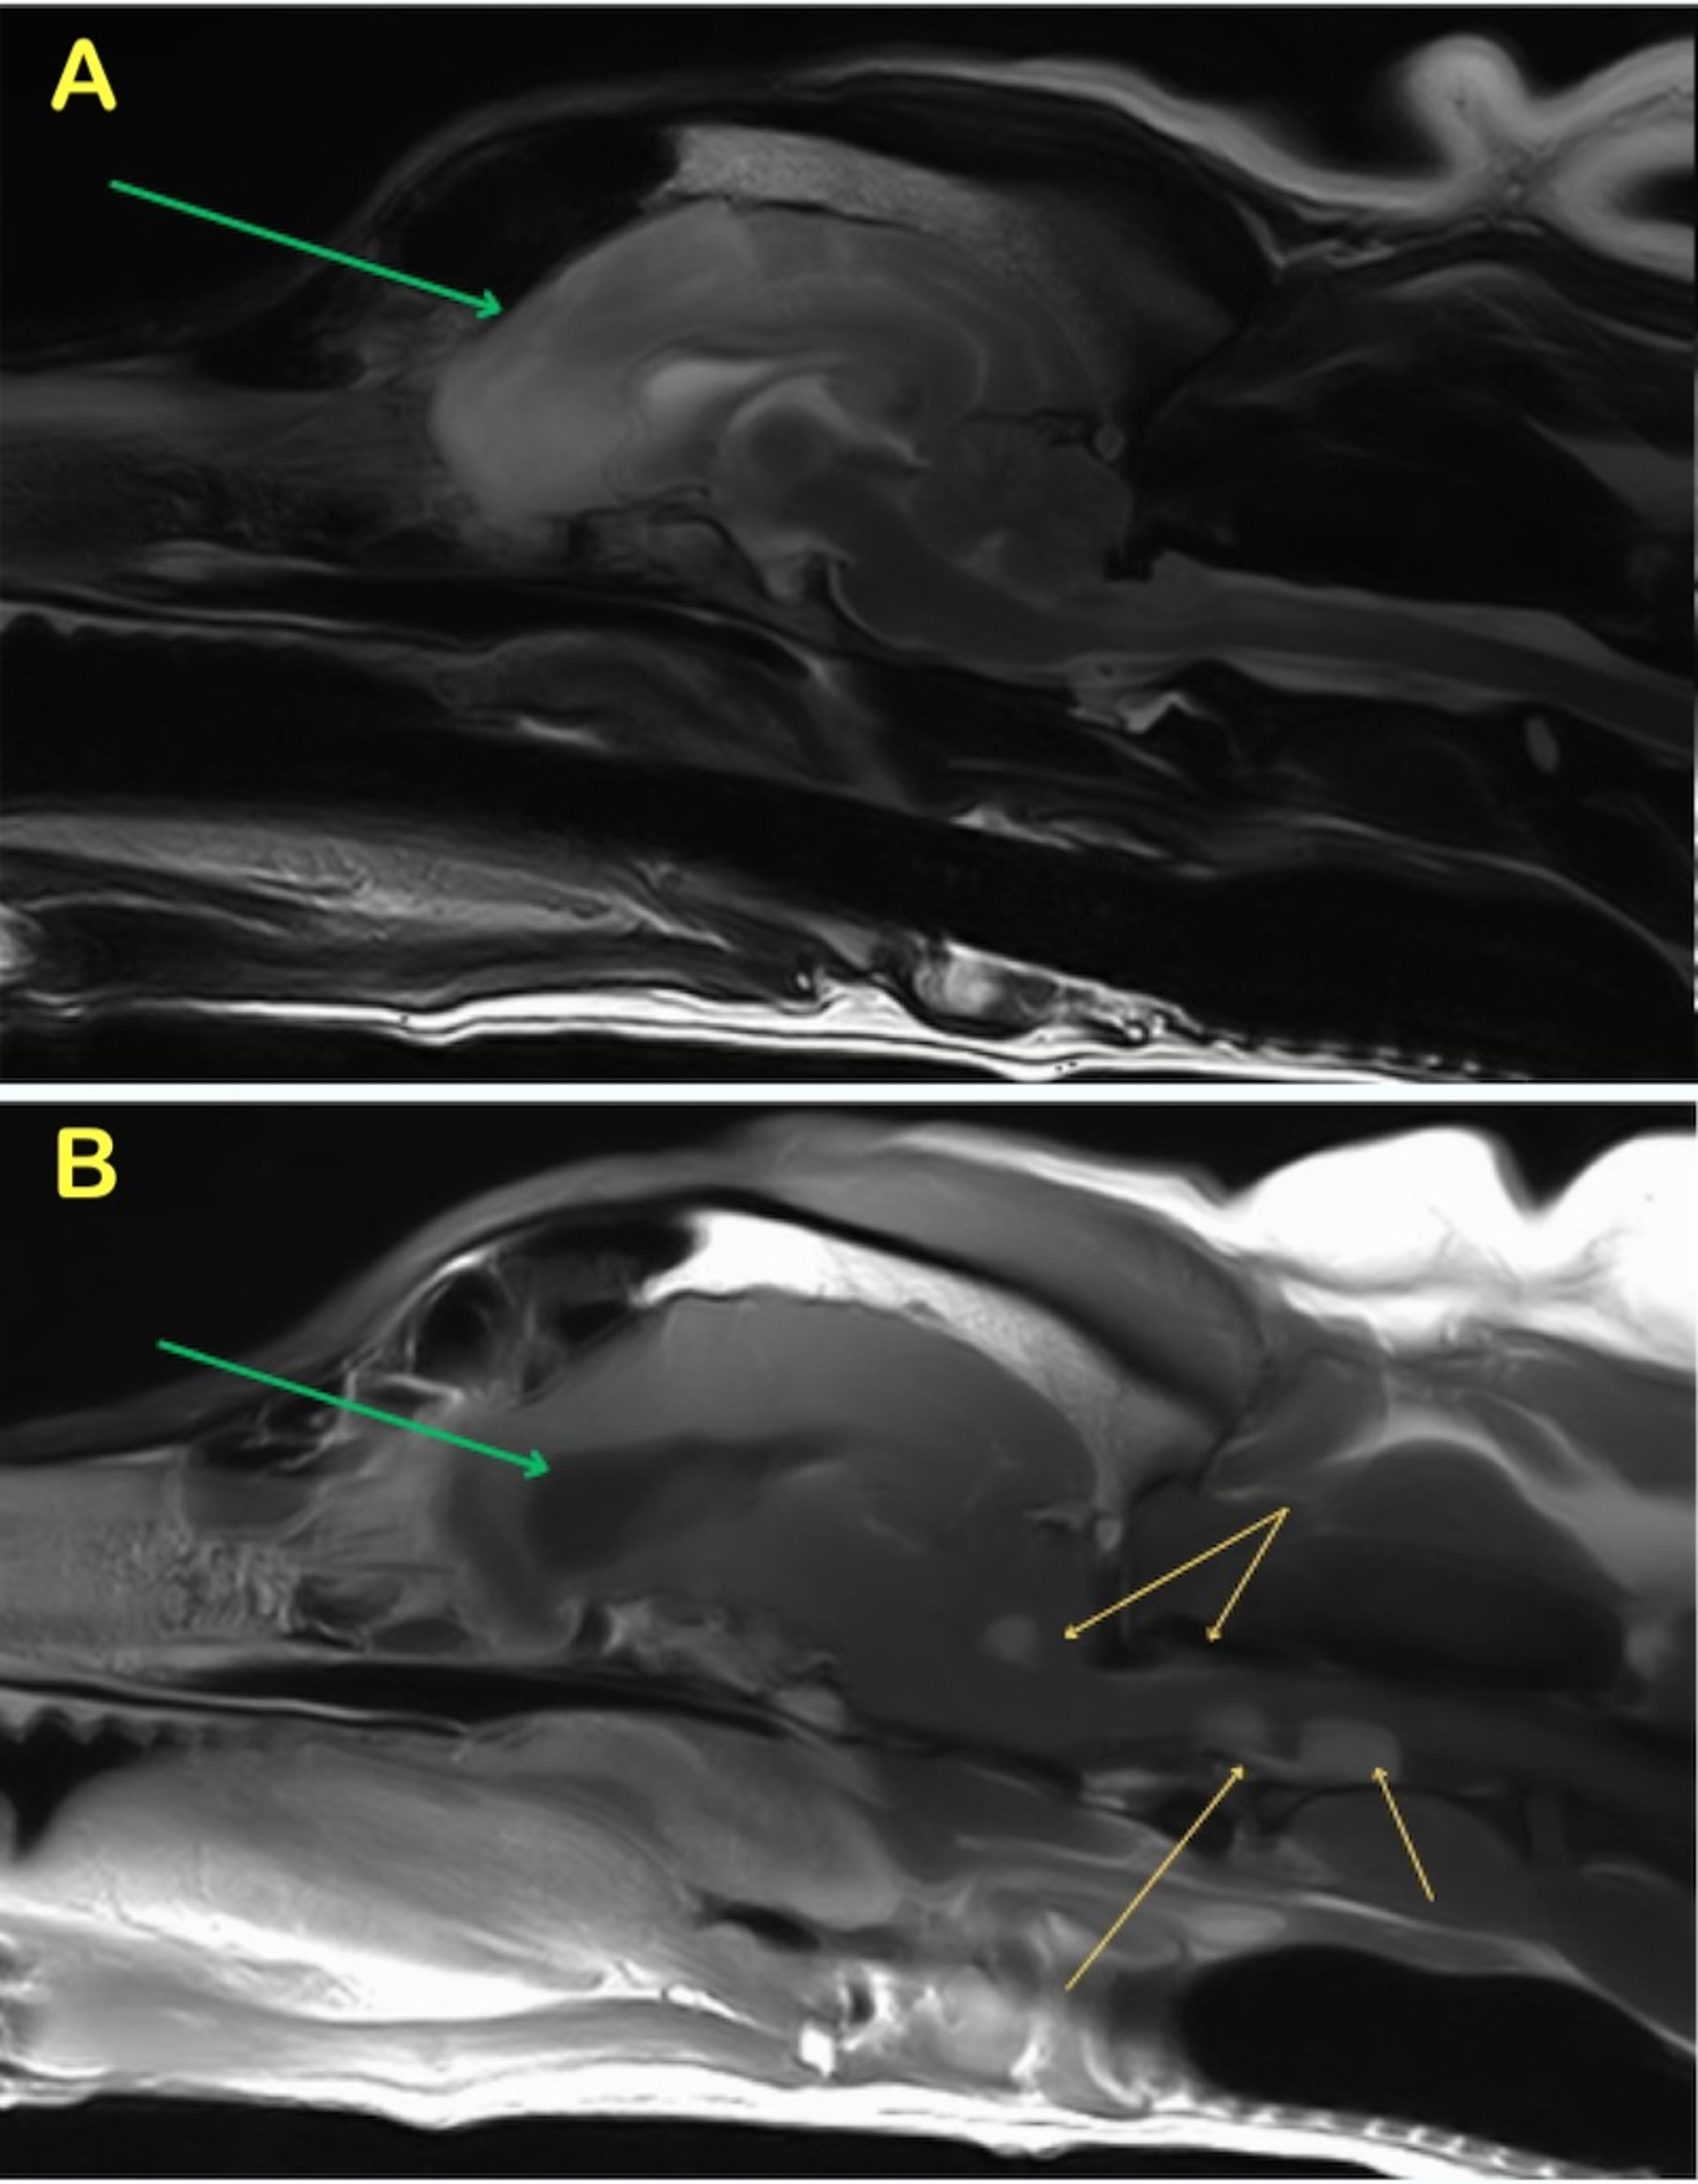

Meningiomas may be distinguishable from tumors within the brain parenchyma on contrast CT scans by their appearance as broad-based, peripherally located masses. Cystic and edematous meningiomas have been detected using CT and MRI. When a "dural tail" (a linear enhancement of thickened dura mater adjacent to an extra-axial mass) is detected by MRI, a meningioma is the most likely cause.

Solitary extra-axial, meningeal-based lesions (meningioma, histiocytic sarcoma, lymphoma, solitary brain metastasis, granular cell tumor, hemangioblastoma, and embryonal tumor) share characteristic imaging features, including broad contact with the dural base, absence of normal brain parenchyma present between the lesion and the dura, expansion into the subarachnoid space, and contrast enhancement. A dural tail sign (a linear region of thickened and enhancing dura mater on postcontrast imaging extending away from the center of the lesion) also commonly occurs, although it is not pathognomonic (39, 40, 41).

A key feature on MRI is the presence of brain tissue between the lesion borders and the meninges (42, 43). A "claw sign" occurs when an expansile lesion with an organ creates thinning of the surrounding parenchyma. Intracranially, this occurs from the formation of a sharp angle at the border of the lesion and the pial surface.

The majority of gliomas have been documented in the forebrain. Compared with astrocytomas, canine oligodendrogliomas are more likely to be T1W hypointense, associated with smooth margins, contacting the ventricles or brain surface, and distorting the ventricles, and less likely to be associated with severe peritumoral edema (3, 44, 45). Contrast enhancement is variable, but a ring-enhancing pattern, where only the periphery of the lesion enhances, is typically associated with gliomas; however, it can be associated with other lesions (eg, abscesses) as well (46).